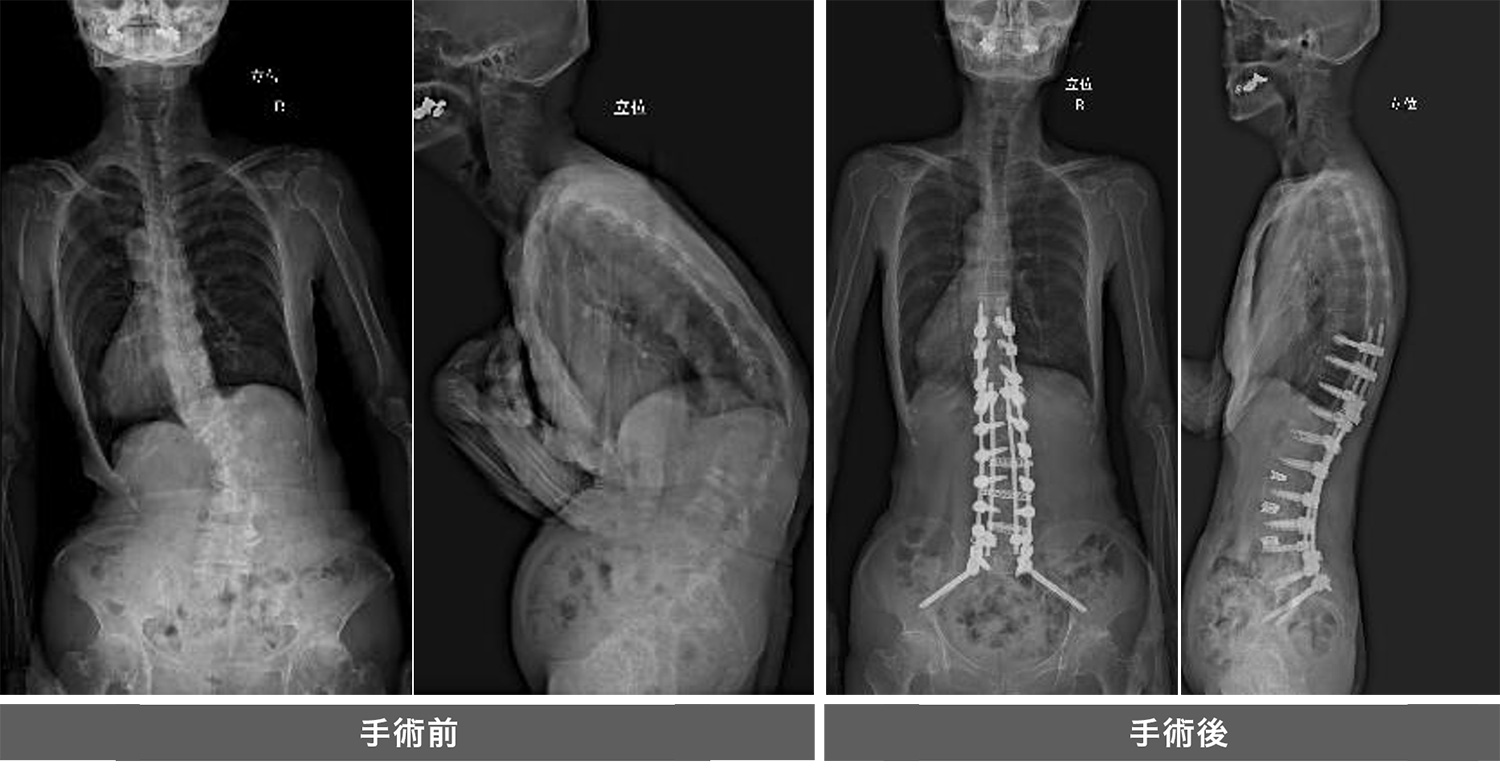

成人脊柱変形や思春期特発性側弯症に対しては矯正固定術を行っております。